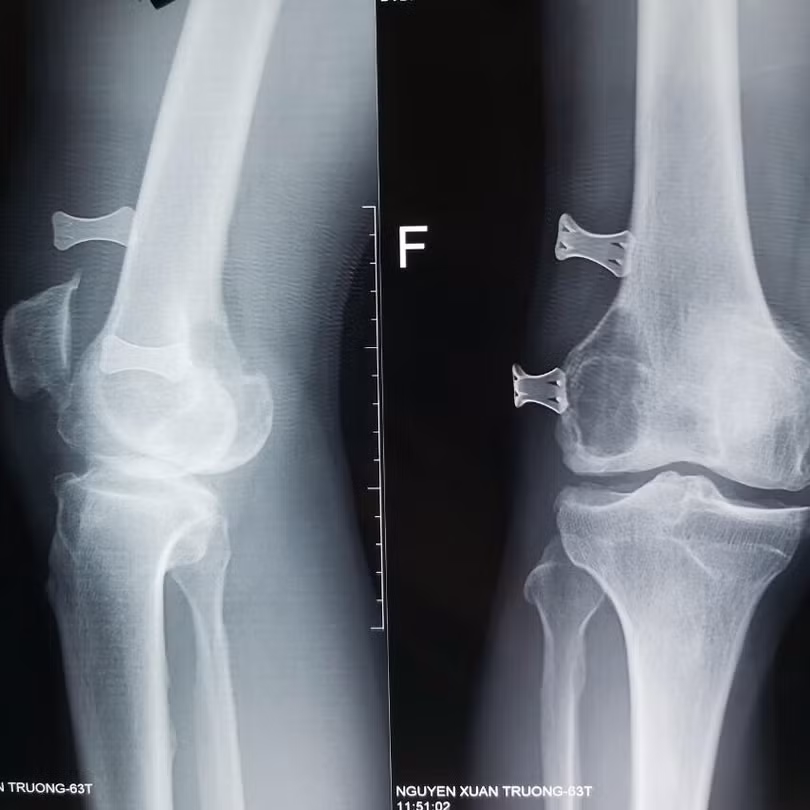

| Phim chụp X-quang khớp gối của bệnh nhân (Ảnh: BVCC) |

Bệnh nhân là ông N.X.T., 63 tuổi, sống ở phường Kỳ Bá, TP. Thái Bình. Trước đó, ông T. có tiền sử đau khớp gối đã 5 năm. Ông T. đã đi nhiều bệnh viện khác và chỉ điều trị nội khoa. Trước khi đến Bệnh viện Hữu nghị Việt Đức1 tuần, ông T. trượt chân ngã, đau đớn, không thể vận động nhiều, khớp gối chỉ gấp được 20°, trong khi bình thường khớp gối có thể gấp được 100° - 120°. Trên phim X-quang cho thấy bệnh nhân vừa bị thoái hóa khớp gối vừa có một khối u ở lồi cầu ngoài xương đùi.

Sau khi chẩn đoán kỹ, các bác sĩ đã quyết định xử lý cùng lúc 2 vấn đề này. Trong quá trình mổ, khớp gối của bệnh nhân có rất nhiều máu, khoảng 200 cc nước máu. Kiểm tra thấy khối u nang xương lồi cầu ngoài xương đùi và mảnh xương bị gãy hẳn ra gây chảy máu trong khớp. Sau khi bơm rửa làm sạch, các bác sĩ đã tiến hành đồng thời phẫu thuật vừa lấy u, vừa làm sạch tổ chức u, ghép xương vào chỗ khuyết, xử lý đồng thời thoái hóa khớp gối.